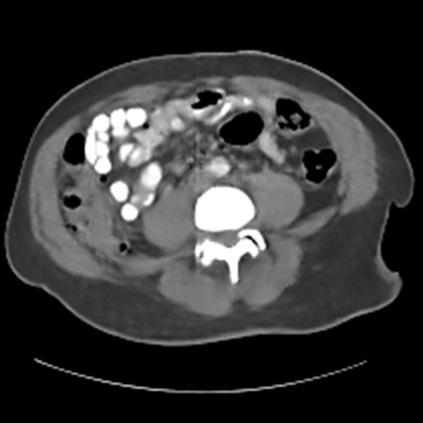

Sparse-view computed tomography (CT) -- using a small number of projections for tomographic reconstruction -- enables much lower radiation dose to patients and accelerated data acquisition. The reconstructed images, however, suffer from strong artifacts, greatly limiting their diagnostic value. Current trends for sparse-view CT turn to the raw data for better information recovery. The resultant dual-domain methods, nonetheless, suffer from secondary artifacts, especially in ultra-sparse view scenarios, and their generalization to other scanners/protocols is greatly limited. A crucial question arises: have the image post-processing methods reached the limit? Our answer is not yet. In this paper, we stick to image post-processing methods due to great flexibility and propose global representation (GloRe) distillation framework for sparse-view CT, termed GloReDi. First, we propose to learn GloRe with Fourier convolution, so each element in GloRe has an image-wide receptive field. Second, unlike methods that only use the full-view images for supervision, we propose to distill GloRe from intermediate-view reconstructed images that are readily available but not explored in previous literature. The success of GloRe distillation is attributed to two key components: representation directional distillation to align the GloRe directions, and band-pass-specific contrastive distillation to gain clinically important details. Extensive experiments demonstrate the superiority of the proposed GloReDi over the state-of-the-art methods, including dual-domain ones. The source code is available at https://github.com/longzilicart/GloReDi.